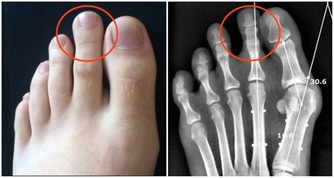

二十五、齦上潔治和齦下刮治之後,很多人會發現牙齒的縫隙變大了,很多人就會誤解為洗牙會把縫隙洗大了。

其實這是一種錯誤的想法,洗牙前沒有感覺到牙齒的縫隙是因為那些縫隙裡面填滿了牙結石,舌頭舔上去感覺不到,當結石清除后,縫隙就會顯露出來。

二十七、這張圖片顯示了牙齦退縮的範圍,其實牙齦的退縮和牙槽骨的吸收是相關的,牙結石的堆積導致牙槽骨的吸收,牙槽骨的吸收又會導致牙齦的退縮和牙根的暴露。